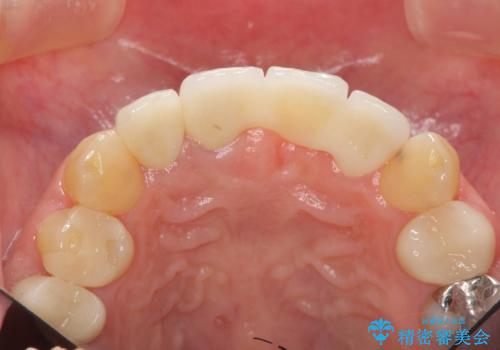

不良インプラントを除去し最終的にブリッジによる補綴で審美性の改善を行うこと、その準備として骨の造成・歯肉の移植による歯の欠損部顎堤のボリュームを維持・増大を計画します。

より審美的な改善を強く求められたため、インプラントを除去し可及的に欠損部顎堤を増大したのちブリッジによる審美改善を行いました。